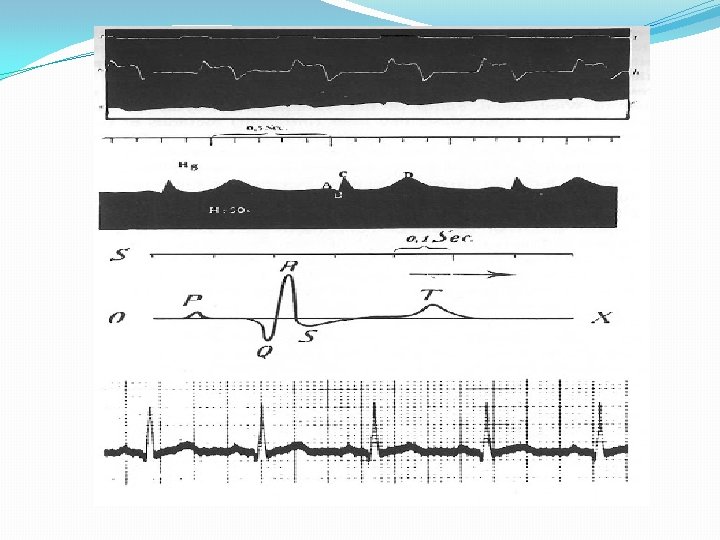

Correlación entre Potencial de Acción Transmembrana y Electrocardiograma.

Correlación entre eventos eléctricos y Electrocardiograma. La repolarización auricular queda oculta en el QRS

Correlación entre eventos eléctricos y Electrocardiograma.